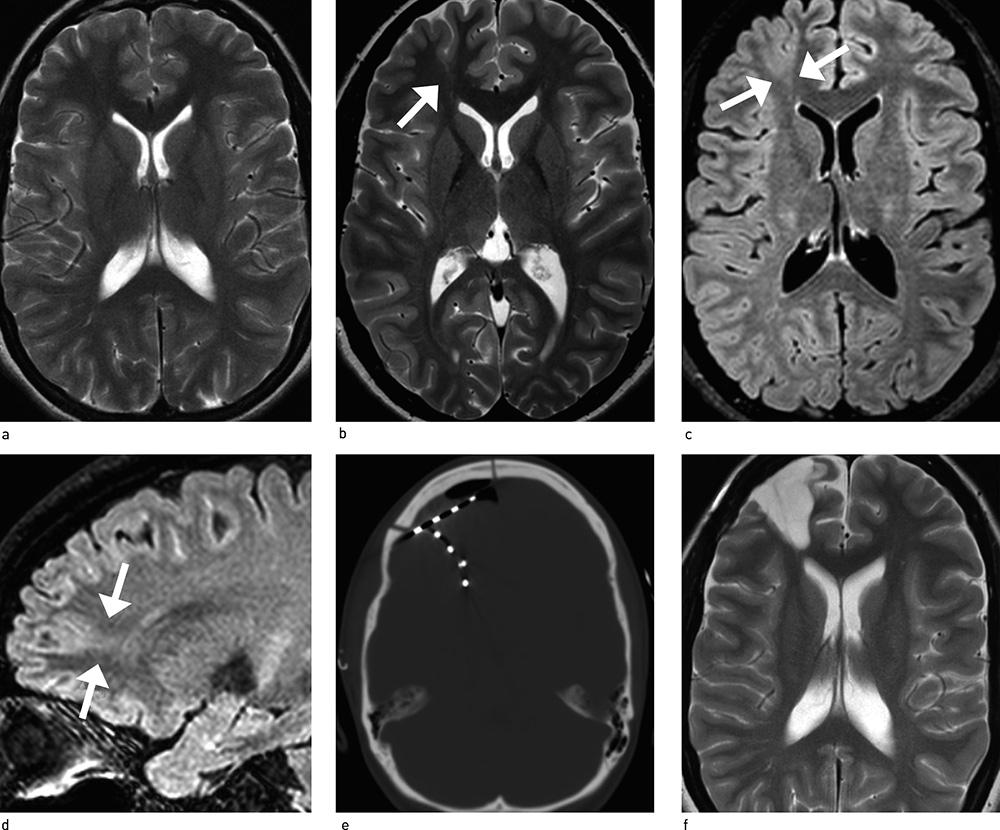

MR-undersøkelse er den viktigste bildediagnostiske metode for påvisning av et morfologisk substrat for epilepsikirurgi. Særlig viktig er undersøkelsen ved temporallappsepilepsi. For å kunne sammenlikne de to sidenes hippocampi legges aksiale snitt etter temporallappens lengdeakse og vinkelrett på denne. T1-vektede volumopptak (MPRAGE) gir best anatomisk fremstilling, og mange små dysplasier kommer godt frem ved T1-MPRAGE. T2- og FLAIR-sekvenser er særlig viktig for påvisning av subtile fokale kortikale dysplasier, noe som i dag er en stor utfordring for nevroradiologene. Innføring av sterkere magnetfeltstyrker, i praksis magneter på 3 tesla fremfor 1,5 tesla, har vist seg å ha stor betydning for påvisning av små lesjoner (fig 1a – f). Med 3 tesla-magneter har vi også fått mer avanserte MR-metoder, eksempelvis traktografi, basert på «diffusion tensor imaging». De nye MR-teknikkene har redusert behovet for invasiv EEG-monitorering (18). Hvis man likevel velger å legge inn intrakraniale elektroder, vil sikrere MR-funn gi bedre og mer målrettede registreringer.

Sjansene for et godt postoperativt resultat er best når funnene fra funksjonsundersøkelser og bildediagnostikk peker mot én epileptogen sone (19). Når funnene er inkonklusive eller sprikende, kan invasive EEG-registreringer fra intrakranialt plasserte elektroder være nødvendig (fig 2). Slike registreringer benyttes hos 10 – 15 % av operasjonskandidatene (ikke-publiserte resultater fra egen avdeling). Bitemporale stripeelektroder (små strimler som plasseres subduralt gjennom borehull) benyttes spesielt hos pasienter med mistenkte temporallappsanfall der skalpregistreringer ikke har gitt sikre funn. Større plater med 20 – 64 elektrodevinduer, såkalte matter, som plasseres subduralt etter kraniotomi, brukes ved mistanke om anfallsstart fra ekstratemporale områder eller lateralt temporalt. Dybdeelektroder (lange nålelektroder) brukes i sjeldne tilfeller når det er mistanke om anfallsstart fra dypereliggende strukturer (fig 1e).